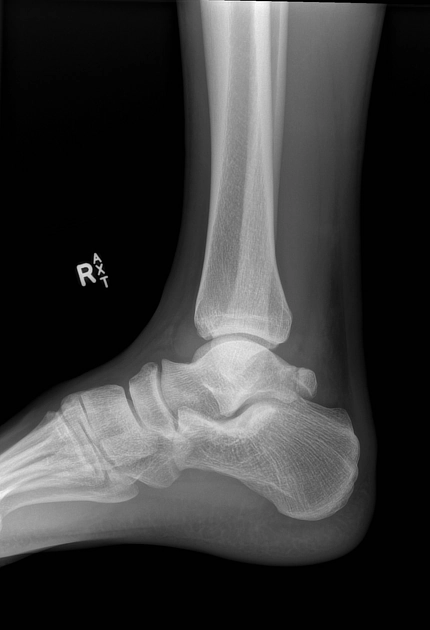

Gãy xương gót (Calcaneal fracture)